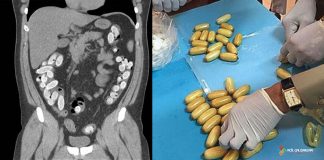

Gastrointestinal Yabancı Cisimler

Acil serviste hem çocuk hem de erişkin hastalarda sıkça karşılaşılan yabancı cisim ve gıda impaksiyonları, çoğunlukla kendiliğinden geçse de bazı durumlarda ciddi komplikasyon riski...